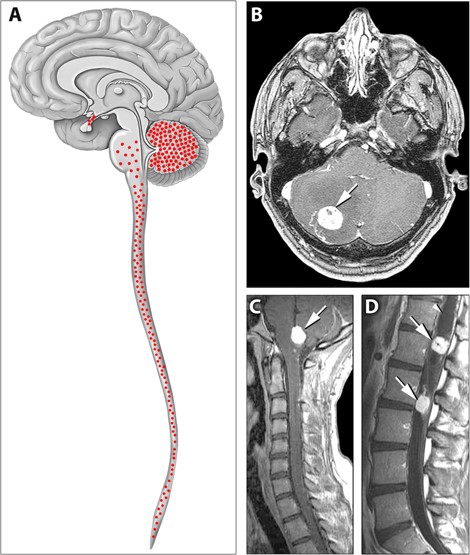

The VHL gene mutation is related to the occurrence of Von Hippe-Lindau disease, a rare multisystem genetic disease. The disease is more serious and fatal, and the average life expectancy of patients with VHL syndrome generally does not exceed 49 years. The main causes of death are rupture and bleeding of central nervous system hemangioblastoma, renal cell carcinoma and malignant hypertension caused by pheochromocytosis.

Distribution of hemangioblastomas in the central nervous systems.Fig.1 Typical distribution of hemangioblastomas in Von Hippel-Lindau disease.1

1. Park, Deric M., et al. "von Hippel-Lindau disease-associated hemangioblastomas are derived from embryologic multipotent cells." PLoS medicine 4.2 (2007): e60. Distributed under Open Access license CC BY 4.0, without modification.